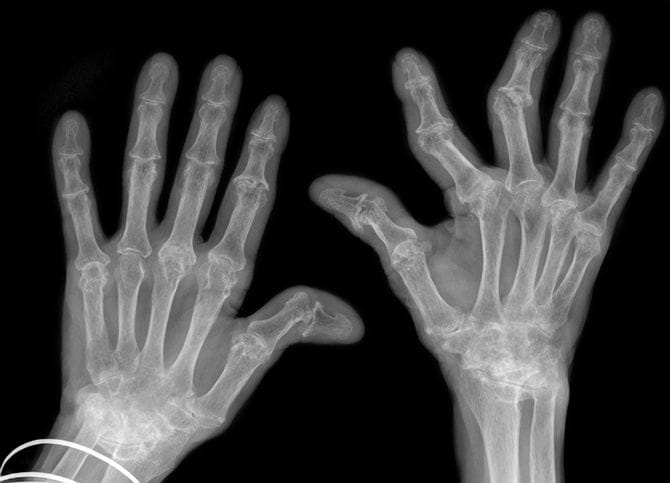

もともと脆弱な関節に強い外力がくわわることで一番心配なのは、腱や靭帯損傷による関節の変位や脱臼、さらには骨折です。

2月4日に会見した木原官房長官によれば「首相は衆院解散後の1月23日に党本部で行われた衆院選立候補予定者への公認証交付で300人以上と握手し、手指の関節が腫れるなど症状が悪化した。衆院選公示後の応援演説で支持者らと握手を重ねる中、右手の指2本の関節が曲がるなどした」とされたからです。

握手等の外力によって「関節が曲がった」となると、これはかなり深刻な事態です。

通常の医師であれば、関節リウマチという基礎疾患のある患者さんが、なんらかの外力で「関節が曲がってしまった」と聞けば、脱臼や最悪の場合骨折もあり得るため、これらを否定するためにも、それこそテーピングする前に、まずはレントゲンを撮ります。